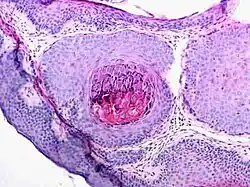

Microscopie

Le molluscum contagiosum réalise une lésion épidermique cratériforme. L'épiderme est épaissi et s'invagine en formant une masse volumineuse constituée de lobules piriformes convergeant vers un puits central[8]. Ces lobules sont constitués de cellules malpighiennes qui contiennent des corps molluscaires basophiles. De la périphérie vers le centre, les cellules perdent leur noyau, deviennent volumineuses, ovoïdes avec un cytoplasme fortement éosinophile devenant basophile. Cet aspect très caractéristique est dû à l'effet pathogène d'un poxviridé. En fonction des incidences de coupe, seules des masses dermiques sans connexion avec l'épiderme peuvent être visibles et ne doivent pas être confondues avec une tumeur.